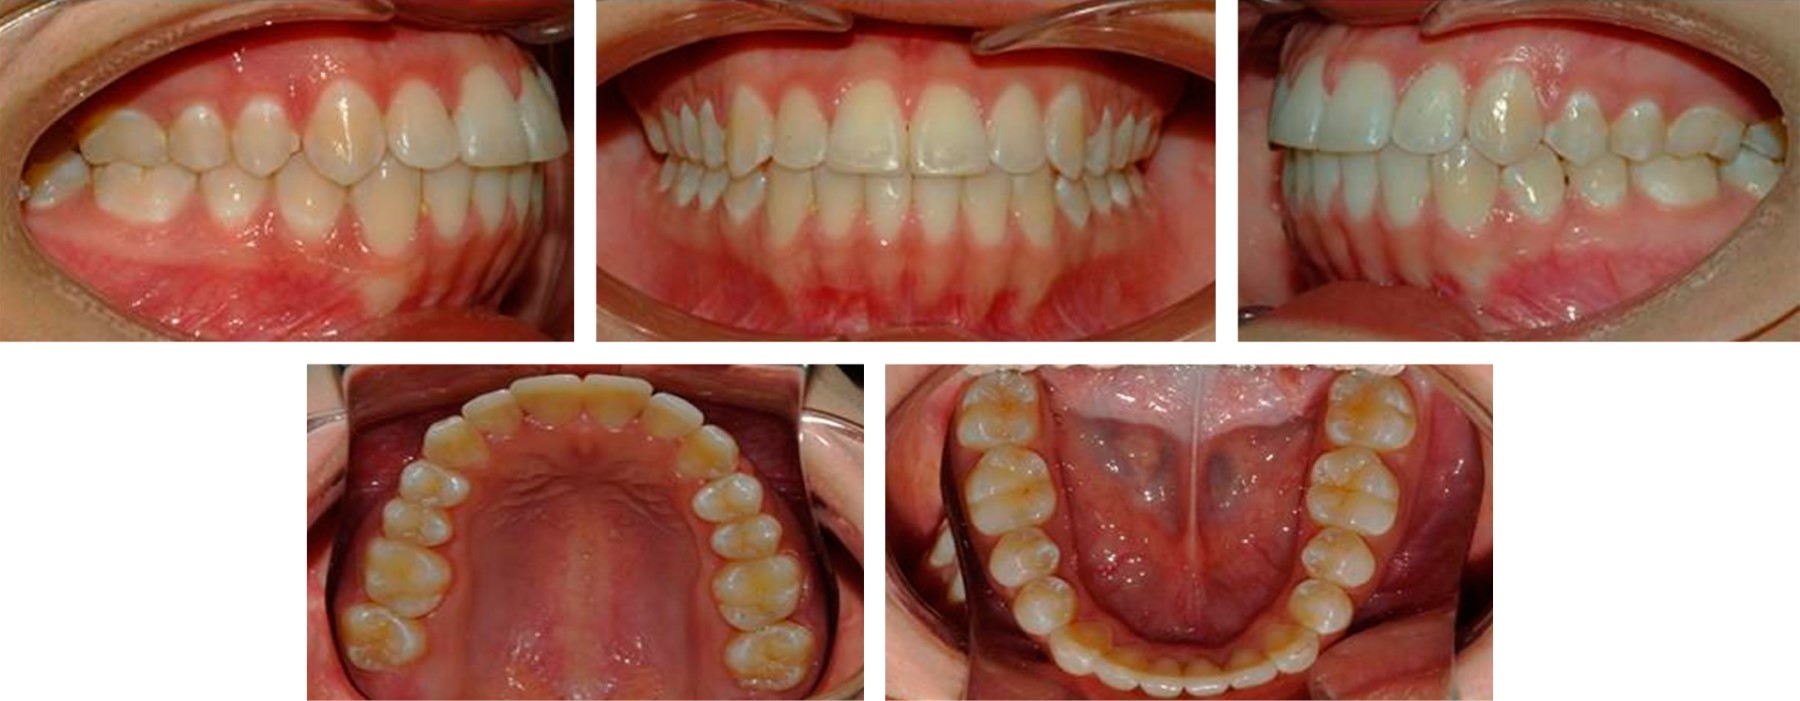

Paciente de sexo femenino de 17 años cuatro meses de edad quien acudió a la Clínica de Ortodoncia de la Universidad Autónoma de Baja California campus Tijuana. El motivo de su consulta fue "quiero arreglar mi sonrisa". La historia clínica la califica como una paciente aparentemente sana. A la inspección clínica se observó biotipo dolicofacial, perfil recto, forma facial ovalada, simétrica, línea media facial y dental inferior no coincidentes, tercio medio aumentado, labios medianos e incompetencia labial (Figura 1).

La evaluación clínica intraoral reportó relación clase I molar y clase III canina bilateral; supraoclusión de los caninos superiores con presencia de apiñamiento moderado; mordida cruzada anterior de los órganos dentarios 22 y 3; línea media inferior desviada hacia el lado izquierdo; falta de coordinación de las arcadas: el arco inferior con forma ovoide y el superior de forma cuadrada (Figura 2).

Figura 2

Figura 3